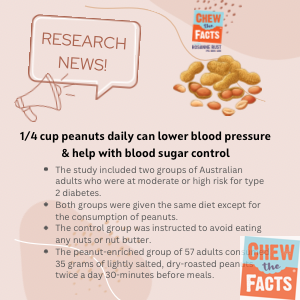

In the United States, the spectrum of health care has been outlined by the Division of Well being and Human Companies as encompassing six ranges of well being care. The first stage of care is preventive care, which is primarily supplied by faculty well being training courses and community and public well being companies. Weight reduction achieved via weight loss plan and train helps management components equivalent to blood sugar , and other problems of weight problems. Avoiding these problems helps decrease blood pressure and prevent high blood pressure.